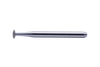

LIFE SAVER BUR (PK5)

LIFE SAVER BUR (PK5)

- A special design to clean any excessive adhesive under the wings without damage the brackets. (when used properly with light force).